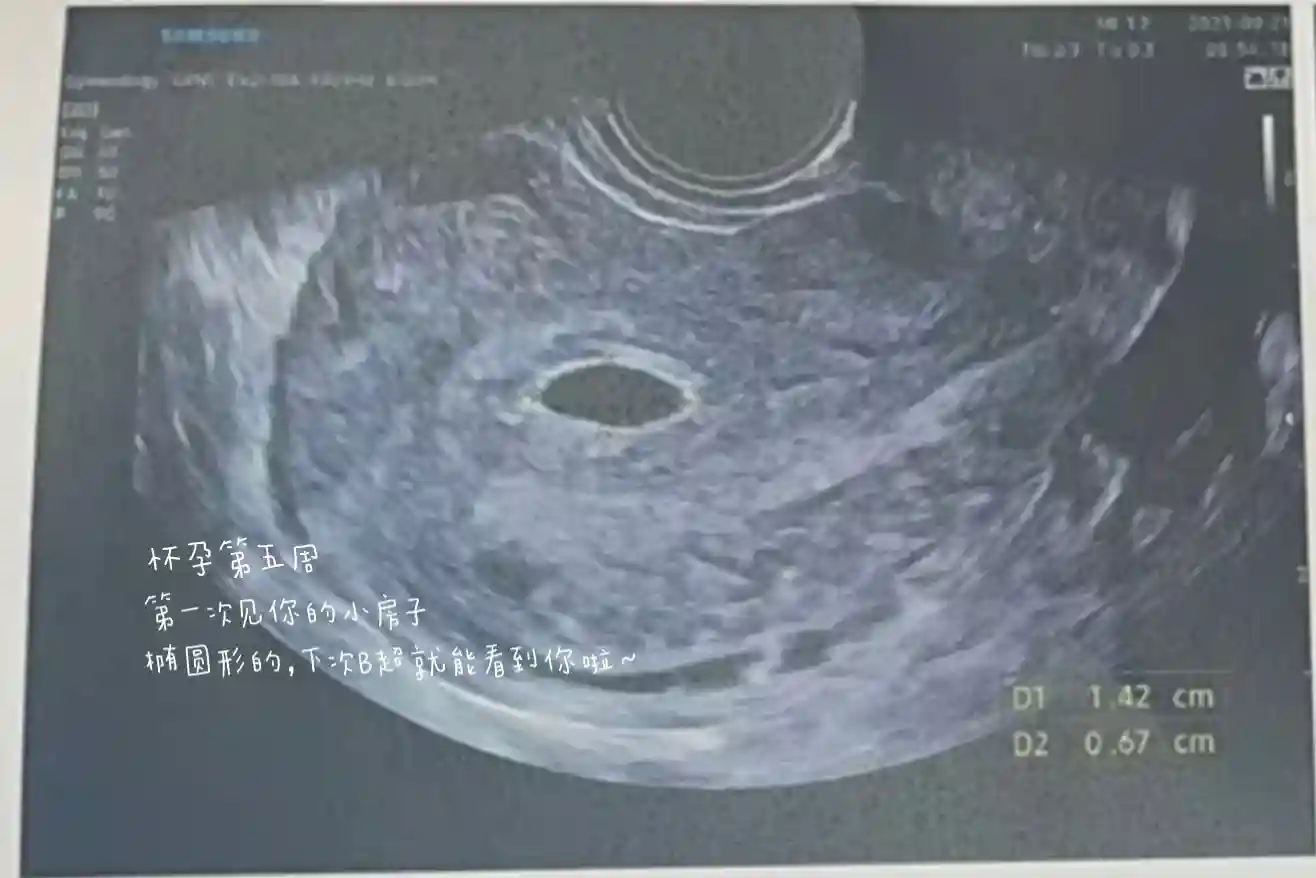

🔸B 超数据:椭圆形孕囊。

🔸肚型:椭圆形,位置靠下,胎位低,肚子上的黑线不直,37周开始长纹儿。